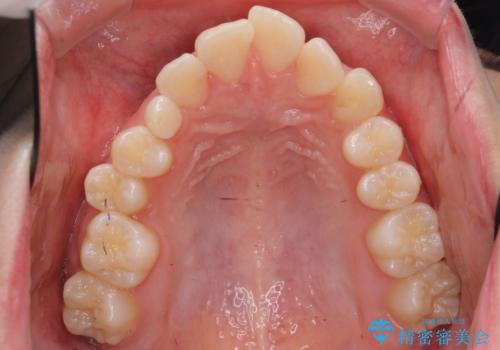

前歯のがたつき 乳歯を抜かずに矯正

- 前歯のがたつきを主訴に来院。

右上に乳歯が残っていましたが、後継永久歯がないため、抜かずに矯正しました。

乳歯の部分が反対咬合でしたが、歯列矯正で被蓋が改善するように移動させました。

右上の乳歯は移動させましたが、幸い矯正後にぐらつくこともなく、そのまま抜けるまで使うことにしました。